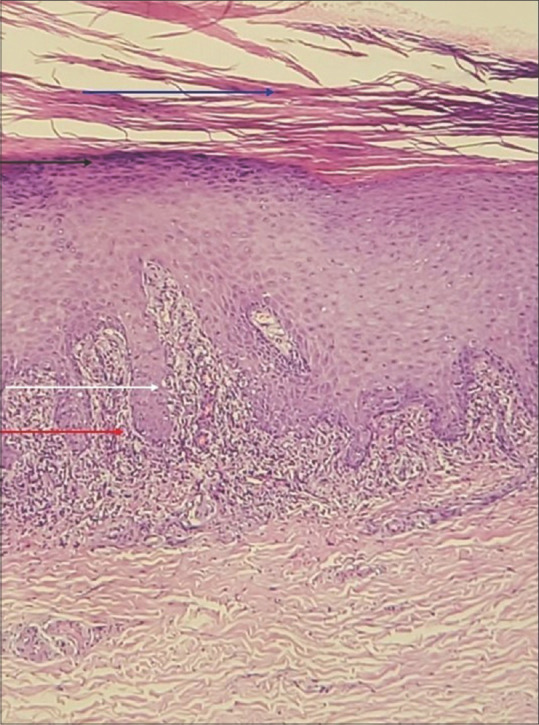

Figure 3.

Photomicrograph showing hyperkeratosis, parakeratosis (blue arrow), acanthosis of the epidermis with wedge-shaped hypergranulosis (black arrow), along with vacuolar degeneration of basal layer (white arrow) with dense band-like chronic inflammatory infiltrate (red arrow) at the dermo-epidermal junction (H and E, 400X)